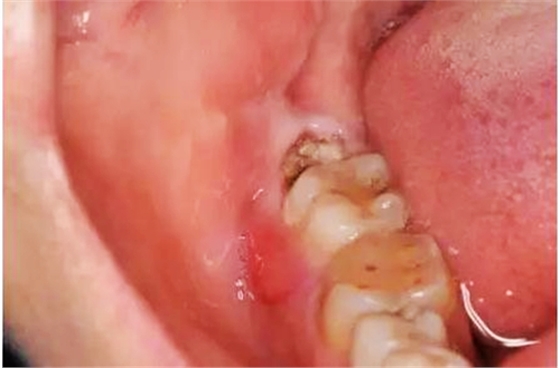

圖1.術(shù)前口內(nèi)觀(guān):48合面齲壞,牙冠萌出1/2,37頰側(cè)牙齦紅腫。